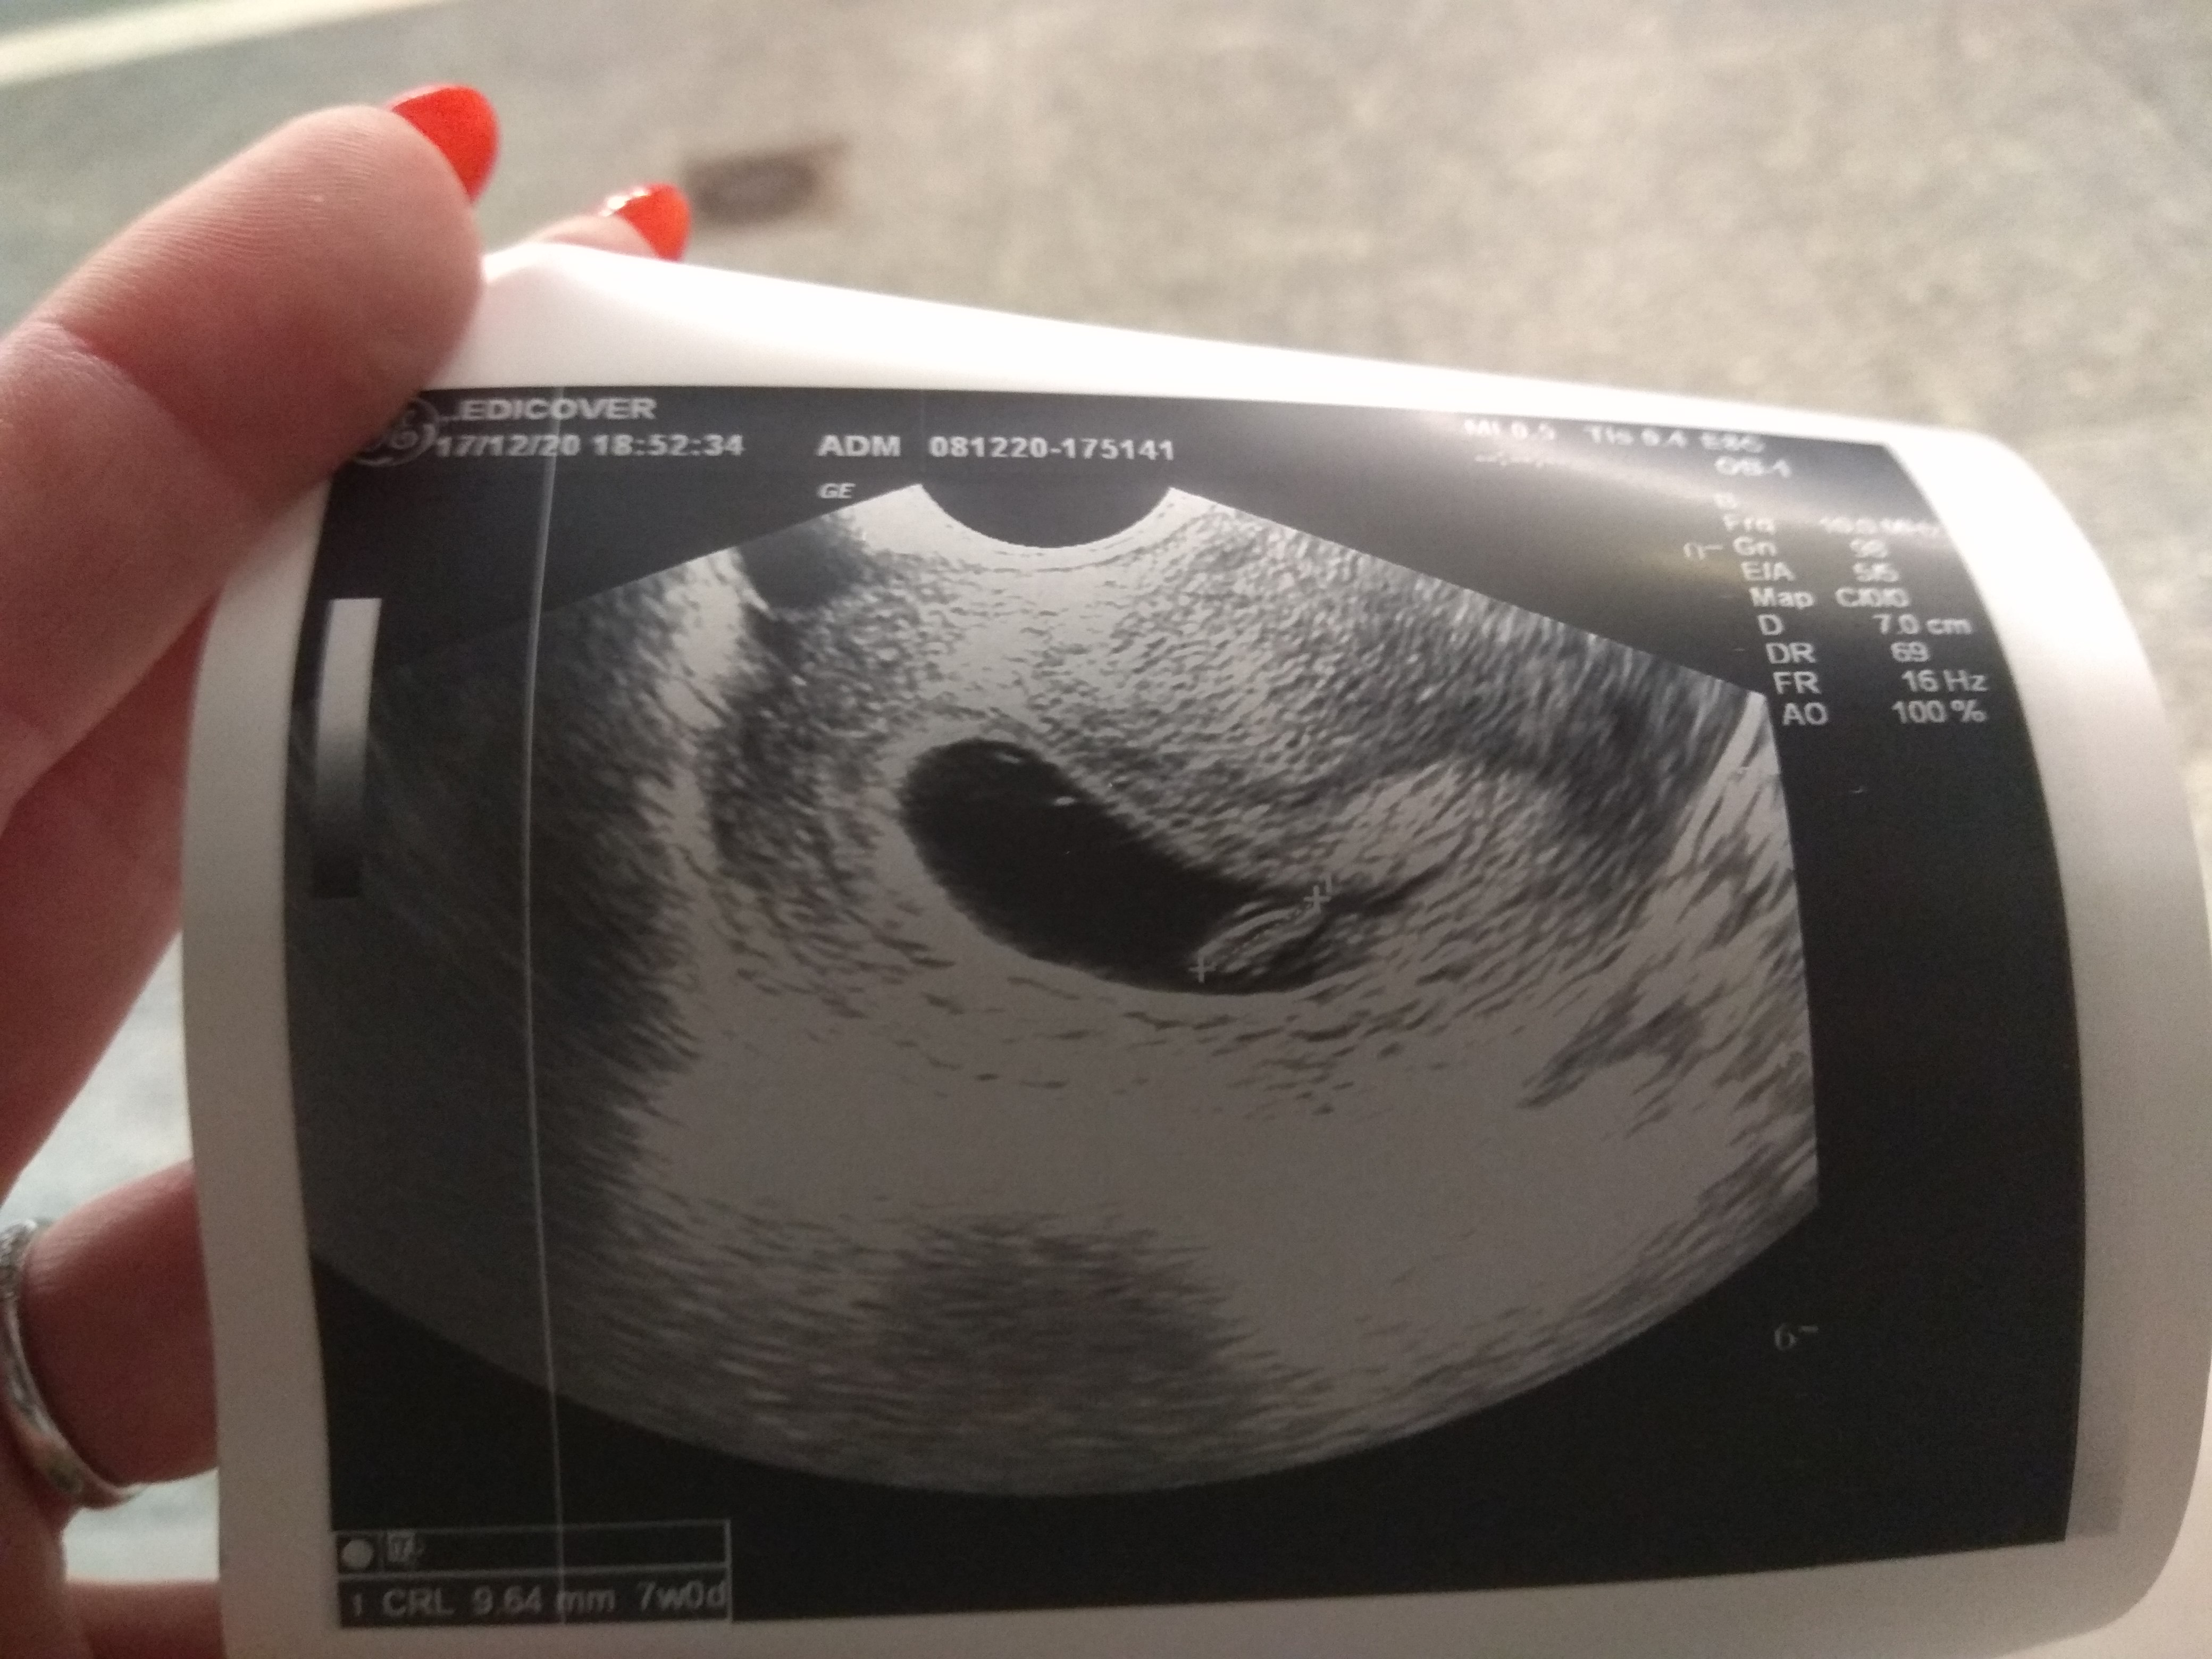

No i jest cały centymetr szczęścia 😁 Serducho wali głośno i wyraźnie 💓

Załączniki

• IMG_20201217_172739.jpg

IMG_20201217_172739.jpg

1,4 MB · Wyświetleń: 116